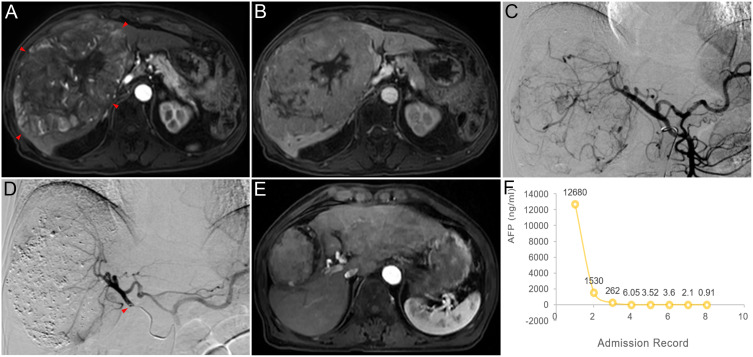

Abstract Image